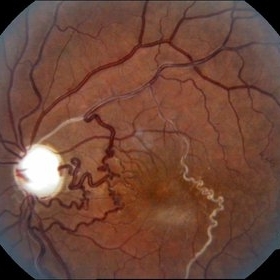

Myopic Degeneration, Macular Hemorrhage

Sep 10 2014 by Mehul A Shah

A 50-year-old male patient presented with complaint of sudden loss of vision.

Photographer: Drashti Netralaya,Dahod

Imaging device: FF 450

Condition/keywords: myopic degeneration